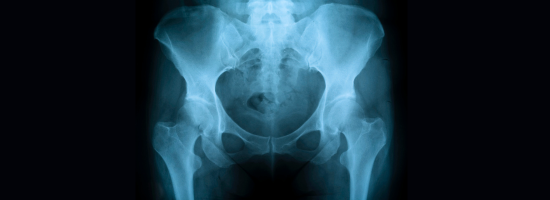

Hip pain doesn’t just slow you down—it can impact everything from walking and sitting to your ability to sleep comfortably. Whether you're dealing with a sports injury, arthritis, or long-term joint wear, expert orthopedic care can make a life-changing difference.

Our hip specialists provide advanced, personalized care to help you move freely and live comfortably. From diagnosis to recovery, we’re with you every step of the way.

Common Hip Conditions We Treat